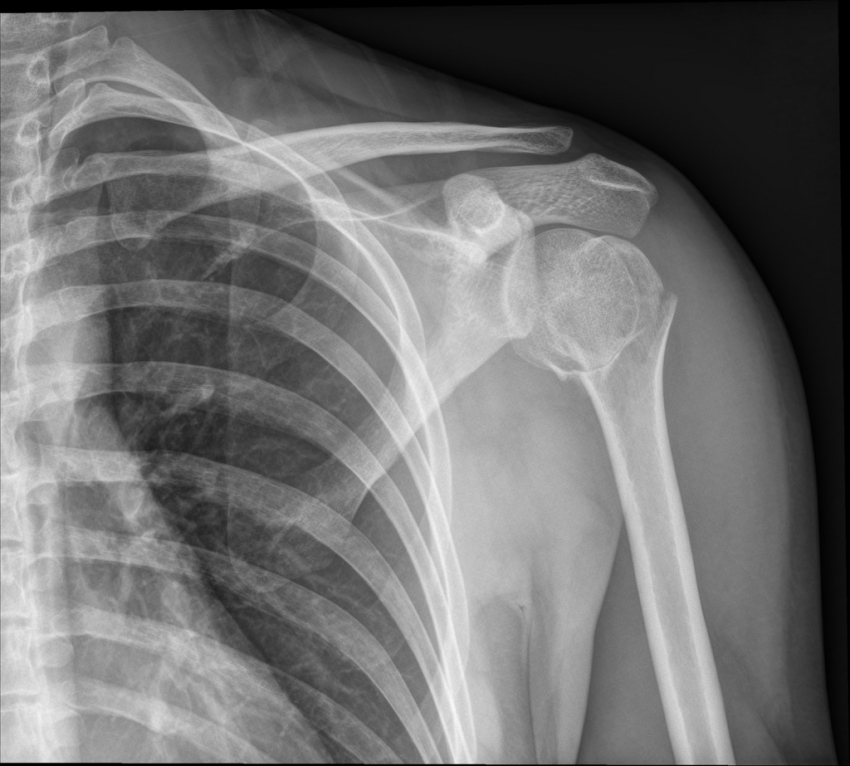

Fracture Dislocation - सांध्यातील एका हाडाला फ्रॅक्चर असल्याने सांधा निखळणे.